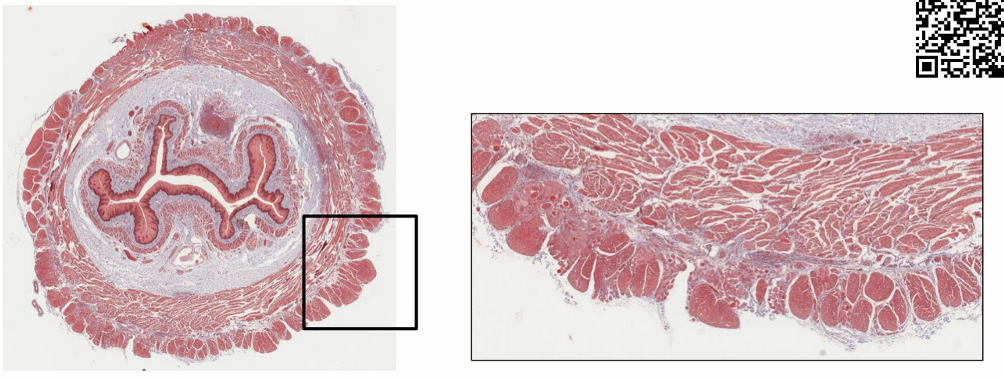

describe the appendix

* tenia coli ends at base of appendix * numerous lymphatic nodules * extend into submucosa * appendicitis * results from blockage of opening to the cecum * scarring, thick mucus or stool

appedix